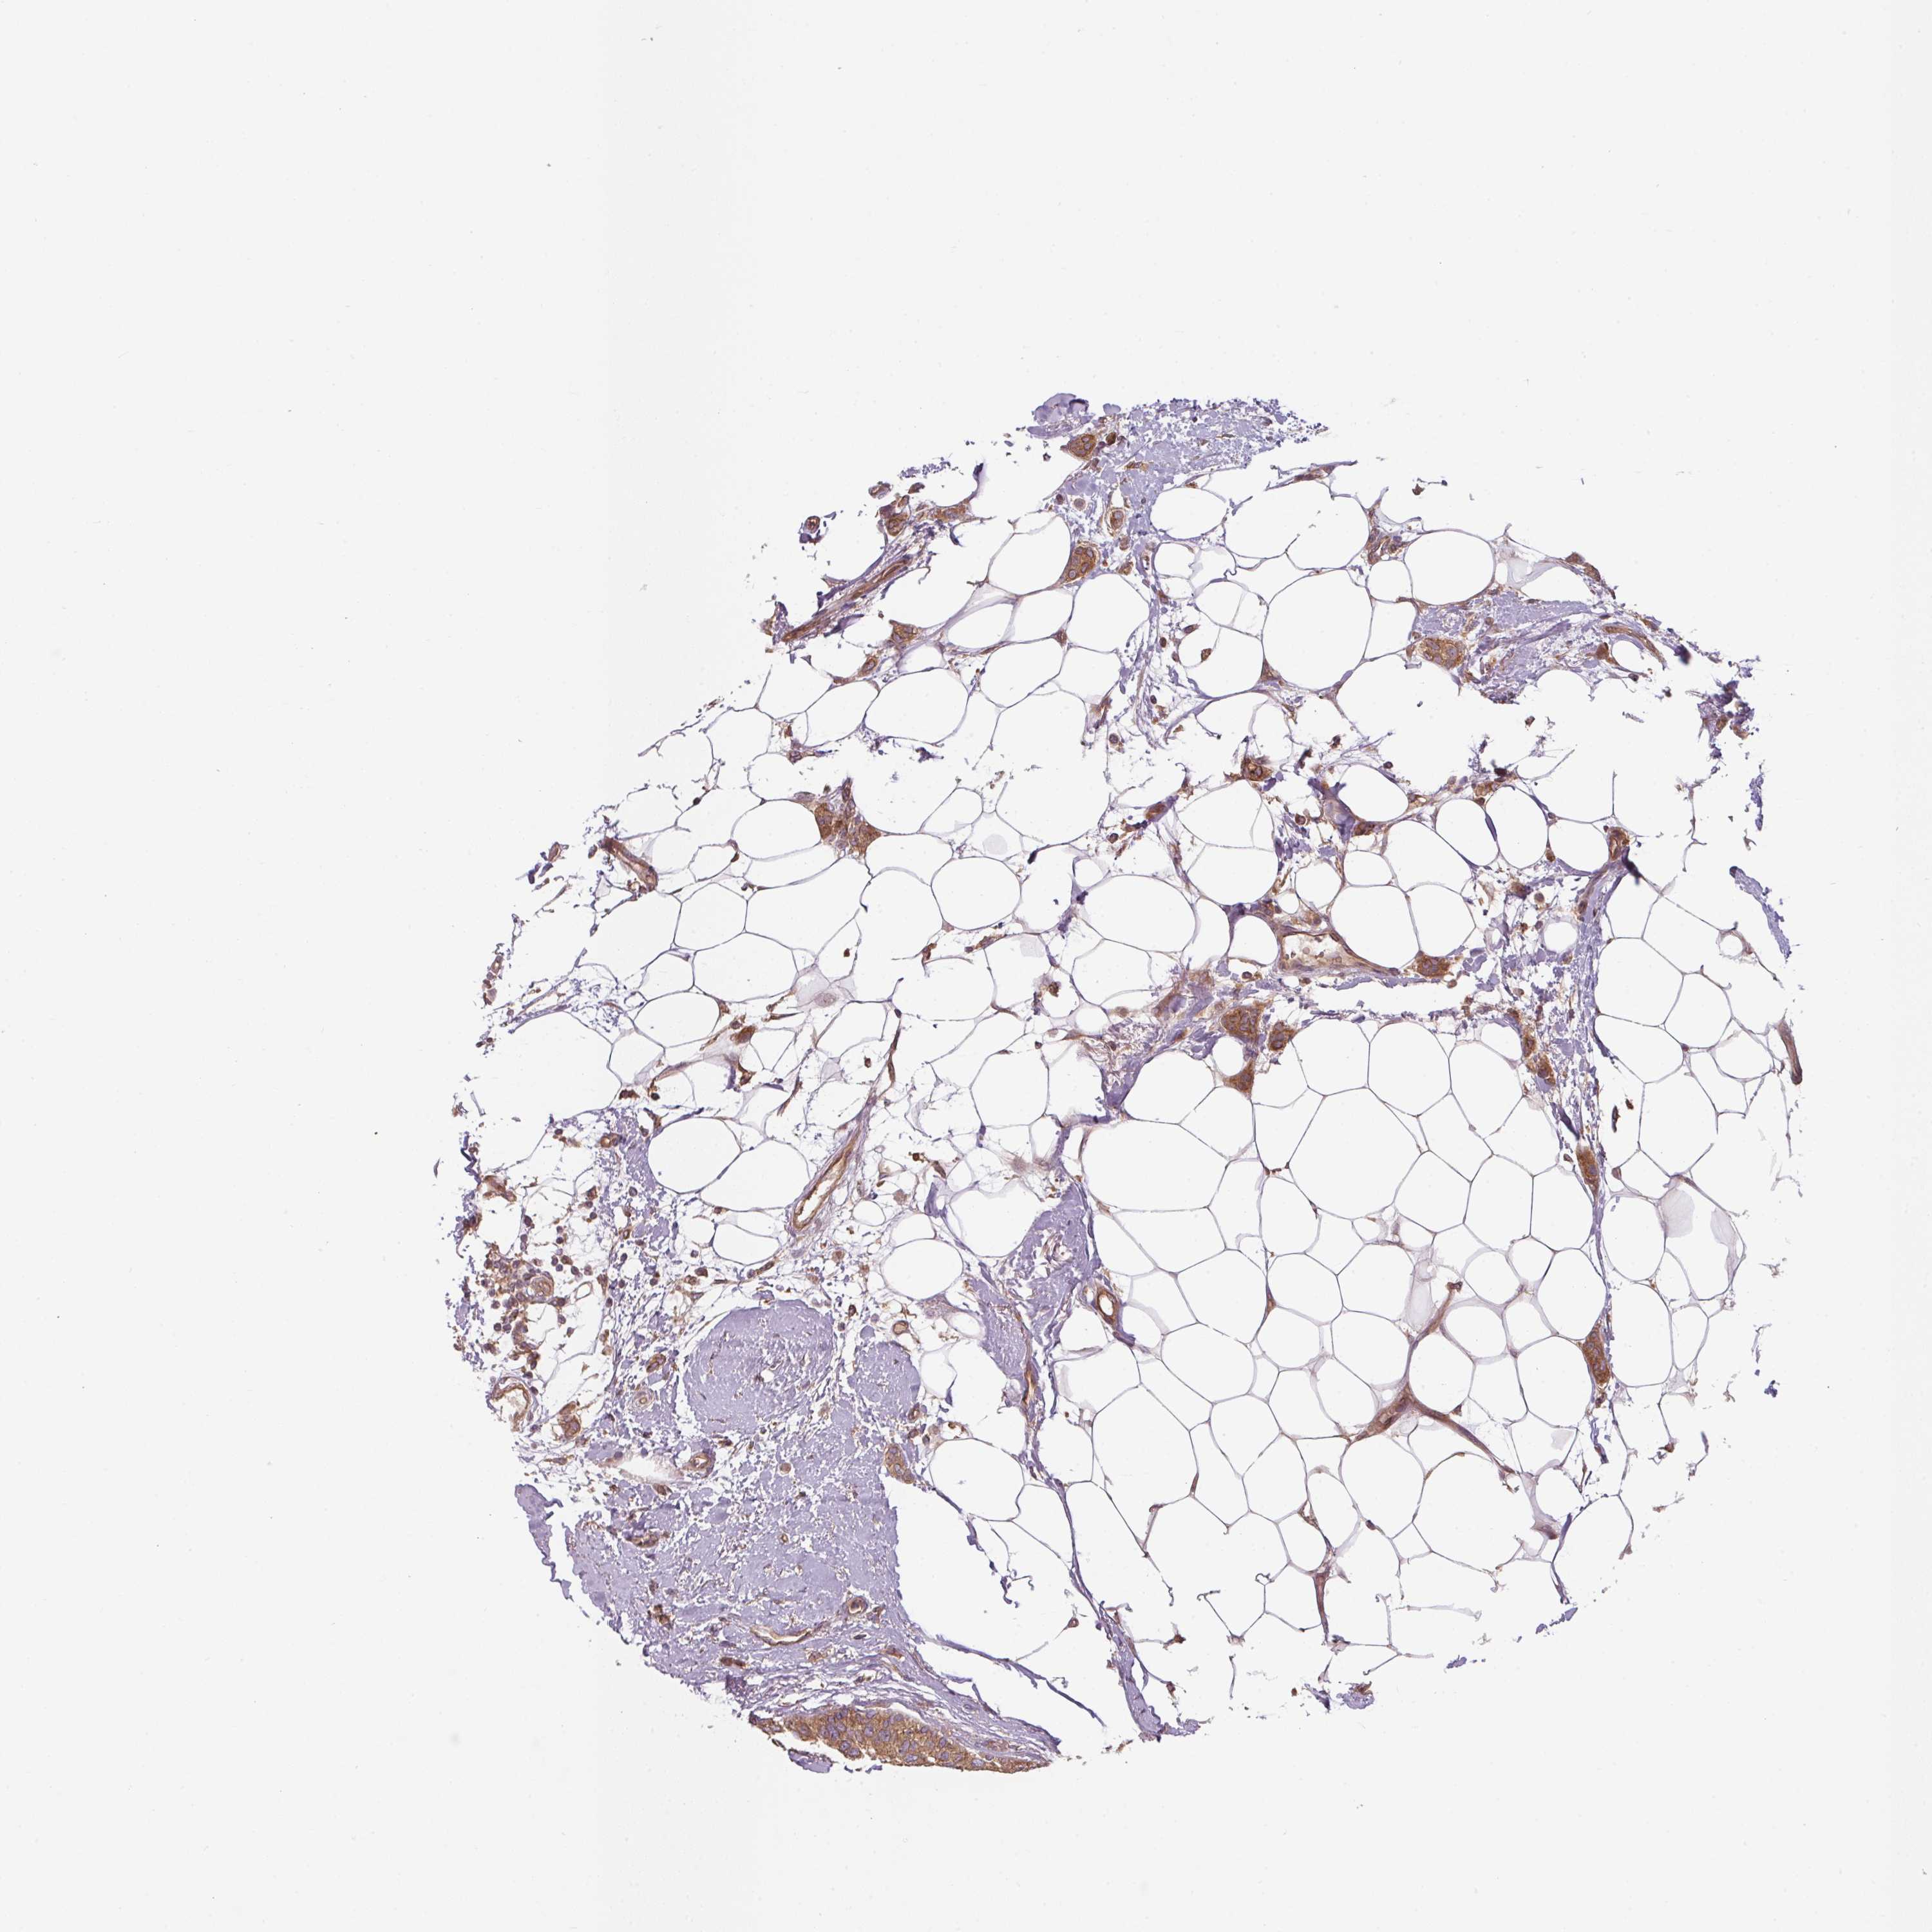

BRCA TCGA BRCA VALIDATION PROTEIN EXPRESSION